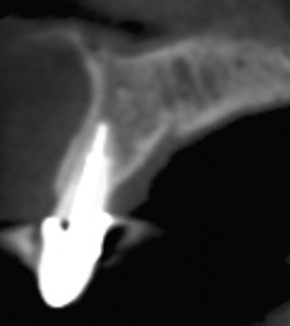

Fig 25. Post-treatment, healthy bone and ideal implant placement were observed radiographically.

Figure 25

Second-stage surgery involved uncovering the implant and finalizing the prosthetic treatment (Figure 24). The ultimate outcome represented a thickened biotype, healthy bone (Figure 25), and an inconspicuous implant-supported crown restoration (Figure 26).